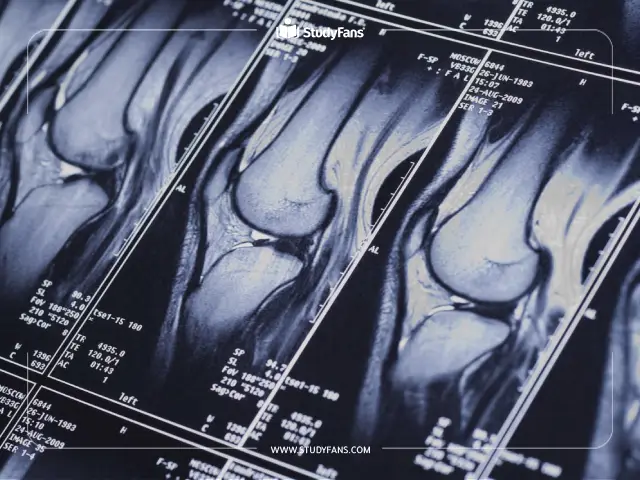

طب الأشعة Radiology

الأشعة التشخيصية Diagnostic Radiology

الأشعة العلاجية Therapeutic Radiology

الأشعة التداخلية Interventional Radiology